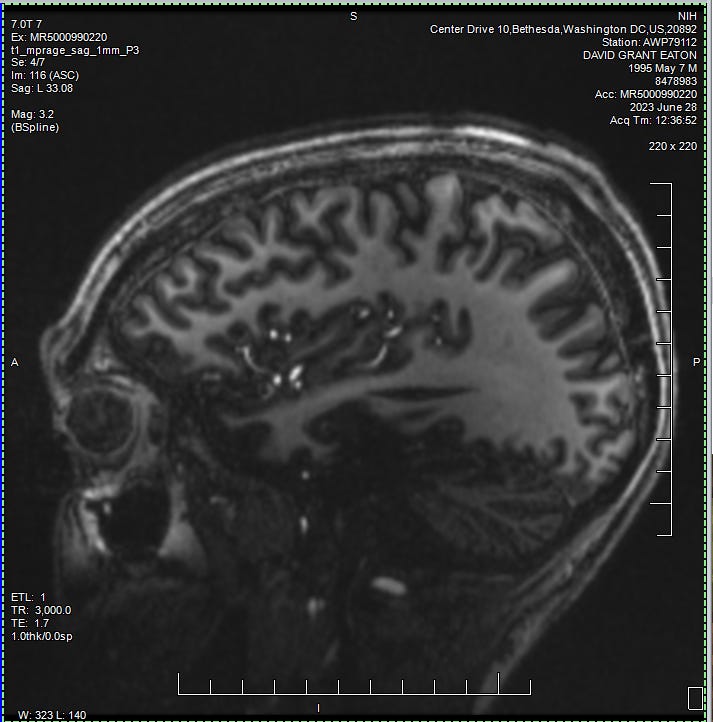

Anyways, Ann comes to introduce herself and brings with her a stack of consent forms. She did a great job of explaining some of the finer details of the studies. Along with their confidentiality practices, compensation, and all of that good stuff. I took a bit of time to read through the paperwork. I knew I was going to sign it anyway. But it's always good to at least glance over the fine print before signing your name away. She also went into the details of what I was going to be experiencing for the remainder of the day. In addition to testing my blood for genealogy, they were also going to get a full baseline of my physical and mental well being. This included a full STI/STD panel, EKG, chest X-ray, COVID test, and physical.

We then headed off of the unit to attend my first rounds of testing. Everywhere I went from this point on required a scan of my wristband, as well as a recitation of my name and date of birth. I did my first ever EKG and Chest X-ray. Zzzzap. I’d never seen such machinery in person before. It was pretty darn cool to see it all in action, and in each of these rooms the operators were super kind and clearly well experienced in their respected fields. I was also surprised that there wasn’t much waiting for these tests. I’m assuming that this study had some kind of priority to move things along rather quickly.